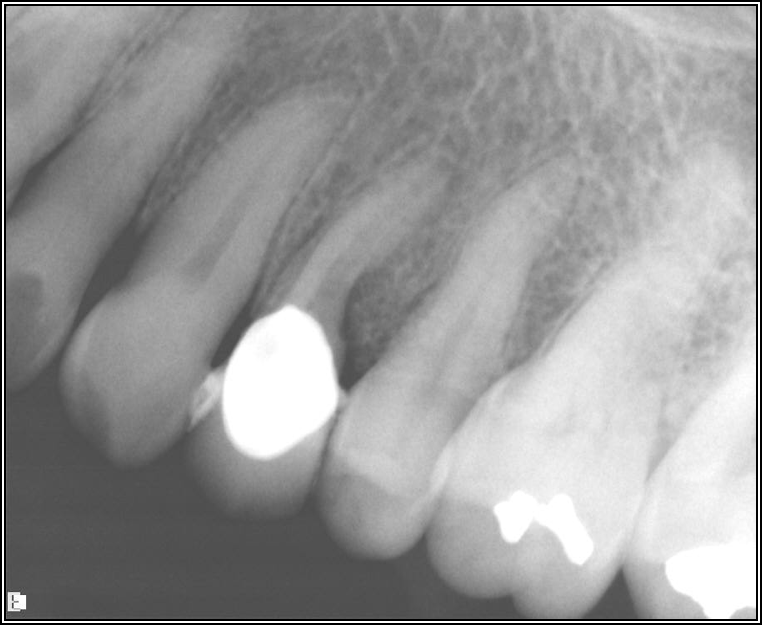

Adjacent Structures

If a tooth stands alone, greater forces will be placed on it because it has no adjacent teeth to provide support. This situation will affect the decision-making process for placing a post. Figure 3 shows a tooth that was on an island and would be having three implants placed in front of it. The tooth would take a much greater beating than another tooth that had support proximally. Even though it had a good root canal, the clinician would need to account for whether the tooth would last until the implants integrated. Figure 4 shows a case that would quickly proceed to implants. The patient had a less-than-ideal bridge for over a decade, with decent endodontics and functionality. There was also an overhang on the premolar. The post was not ideal in this case because there was one distal canal and not all the gutta-percha was removed from it. An intimate fit should be the goal with the post and the walls. Whether using a threaded or non-threaded post, there should not be excess gutta-percha because it is not as solid as the tooth and will lead to greater movement. That movement on the tooth and bridge will create too much force and result in demise.

Fig 3. Tooth on an island.

Figure 3

Fig 4. Case that quickly would proceed to implants.

Figure 4